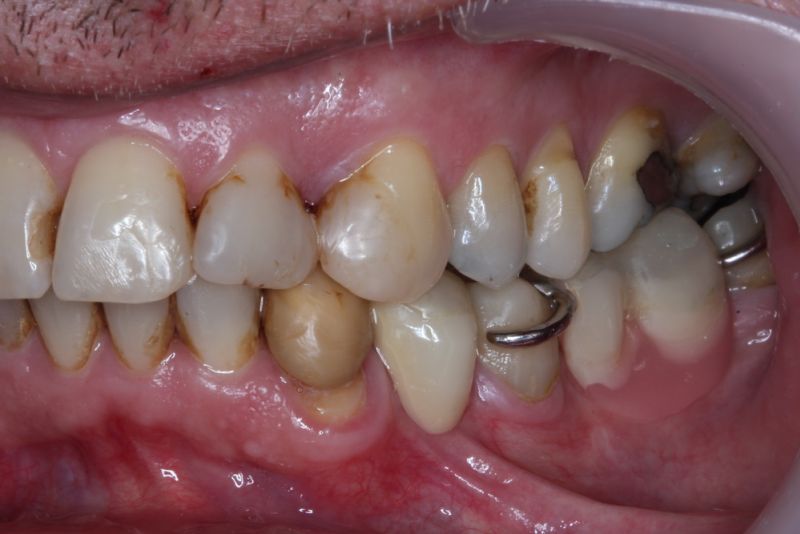

Der Patient hat von einem CMD Spezialisten in Bielefeld einen Aufbissbehelf erhalten. Den hat der Patient mit Zellstoff unterfüttert, weil der Aufbissbehelf so unterschiedlich hoch war, dass der Patient es vor Schmerzen mit dem Aufbissbehelf nicht ausgehalten hat.

Erkennbar ist die massive Abweichung der habituellen Bisslage von der neuromuskulär zentrierten Bisslage.